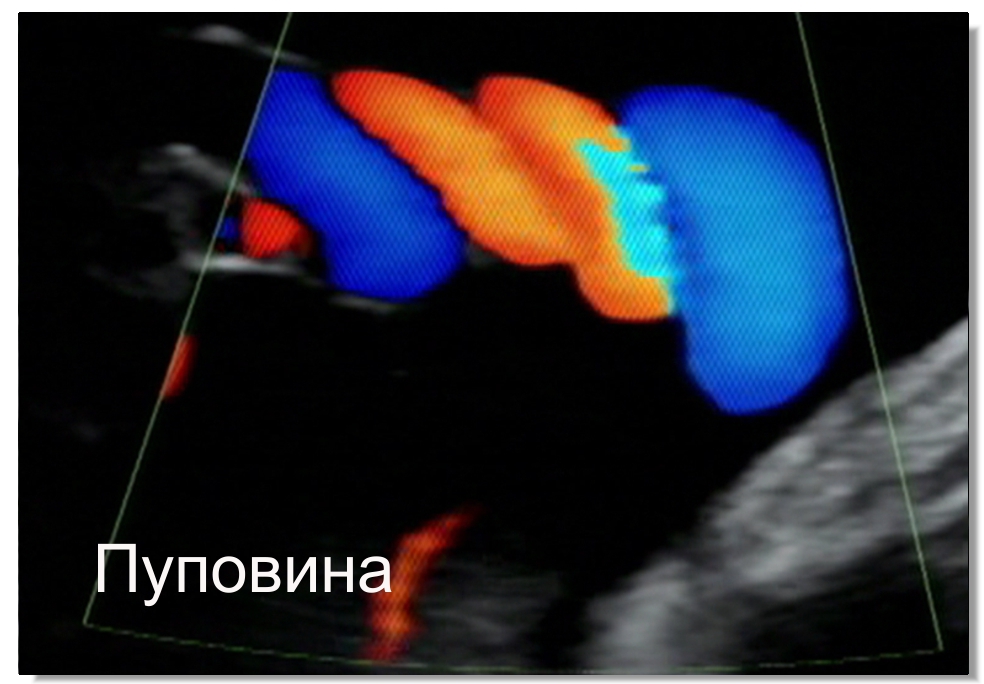

Используя ультразвуковую диагностику плода с допплер исследованем измеряя индексы кровоснабжения артерий пуповины, артерий мозга плода и внутрипеченочного сосуда ductus venosus, возможно оценить благосостояние плода.

Допплер исследование помогает тем будущим мамам, которые стали плохо чувствовать движения плода, и те, кто обеспокоен состоянем плода.